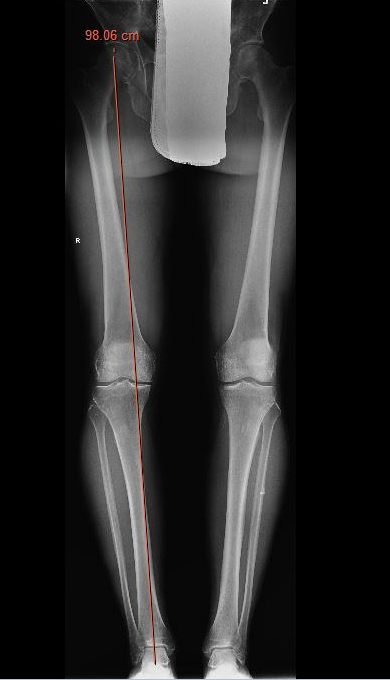

1. Calculate Desired Angle of Correction on Long Leg Views

A. Simple Calculations

Measure anatomic femoral tibial angle

B. Miniaci method

Line A: Desired mechanical axis

- center of the hip to new desired weight bearing axis on lateral tibial plateau

- Fujisawa point (62% from the edge of the medial tibial plateau)

- slightly lateral to the lateral tibial spine

- extend this line to the level of the ankle

Line B: Center of ankle to pivot point on the proximal lateral tibia

Line C: Lateral pivot point to meet Line A

The angle between B and C is the angle of the desired correction